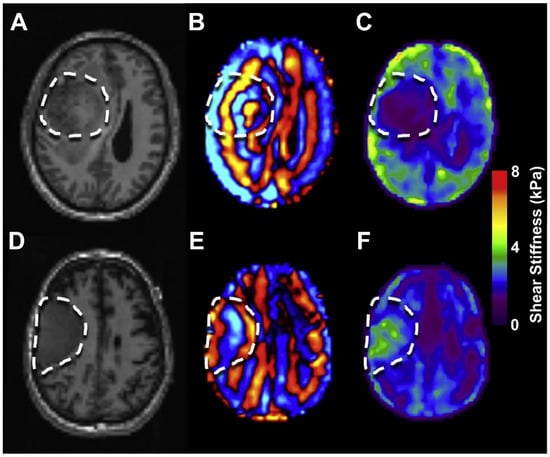

- Streitberger, K.J.; Reiss-Zimmermann, M.; Freimann, F.B.; Bayerl, S.; Guo, J.; Arlt, F.; Wuerfel, J.; Braun, J.; Hoffmann, K.T.; Sack, I. High-resolution mechanical imaging of glioblastoma by multifrequency magnetic resonance elastography. PLoS ONE 2014, 9, e110588. [Google Scholar] [CrossRef]

- Pepin, K.M.; McGee, K.P.; Arani, A.; Lake, D.S.; Glaser, K.J.; Manduca, A.; Parney, I.F.; Ehman, R.L.; Huston, J., 3rd. MR Elastography Analysis of Glioma Stiffness and IDH1-Mutation Status. AJNR Am. J. Neuroradiol. 2018, 39, 31–36. [Google Scholar] [CrossRef]